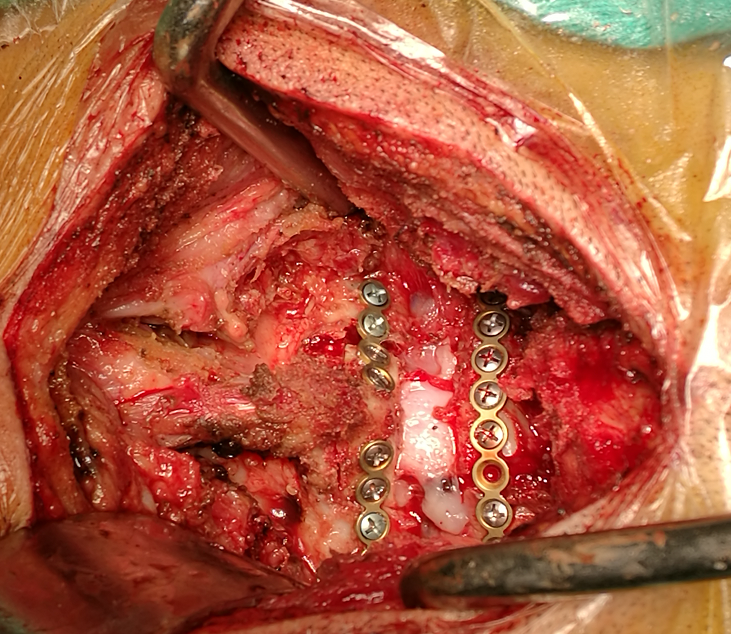

颈椎髓内肿瘤切除椎管切除减压多节段侧块螺钉内固定

图片尺寸411x610